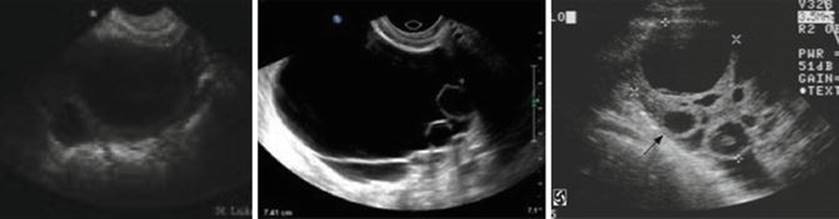

Fig. 2.28

Ovarian hyperstimulation syndrome

Ovarian Hyperstimulation Syndrome (OHSS) (Figs. 2.27d and 2.28)

Ultrasound is essential for the prevention, diagnosis, and monitoring of OHSS. Judicial use of TVS for follicular monitoring while inducing ovulation with gonadotropins remains critical for the prevention of OHSS. TVS is also used to monitor the ovarian volume, keep record of number of follicles and corpus luteum and their size, diagnose ascites and pleural effusion when monitoring for the progress of OHSS. Ultrasound can also be used to guide paracentesis of the ascites or pleural effusion in cases, which develop severe respiratory distress to avoid trauma to ovaries or other abdominal structures.

Functional Cyst (Fig. 2.29)

Functional cyst is diagnosed by the presence of cyst at prestimulation baseline scan on day 2 or 3 of the menstrual cycles following GnRH agonist stimulation for downregulation. It is characterized by sharp edges and anechogenic contents and is due to the initial FSH surge, which occurs after commencement of GnRH agonist in a long downregulation cycle. The presence of a functional cyst requires either cancellation of cycle or an ultrasound-guided aspiration of the cyst before commencing ovulation induction.

Persistent/Retention Cyst (Fig. 2.29)

The presence of cyst at baseline scan suggests a follicle from previous cycle or a persistent corpus luteum. It may result due to growth of the smaller follicles following the hCG trigger. No drugs are administered for ovulation induction in the presence of a retention cyst. It is followed ultrasonographically and if persistent may require medical or surgical treatment.